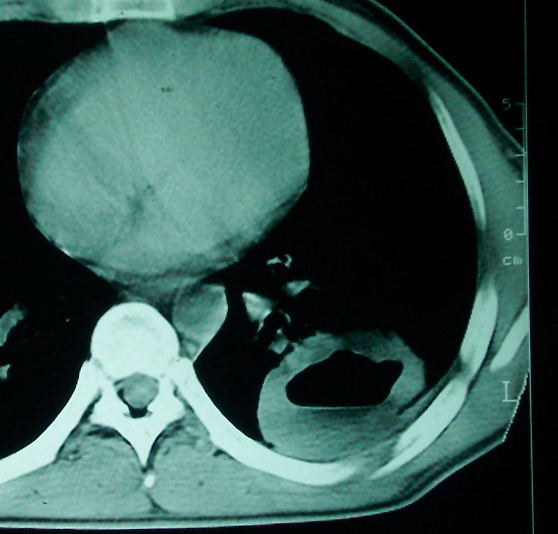

m      37y      发热   咳脓痰月余      ct肺脓肿但住院抗炎治疗后双肺内结节不知该如何解释

治疗后见左肺下野病灶较前缩小但双肺内结节影似无变化请较各位老师该如何下结论    治疗前wbc14.5 治疗后wbc 11.0

空洞内可见小结节样密度影考虑合并真菌感染

左下肺病灶除了明显的厚壁空洞 气液平外,明显见壁结节,另两肺多发小结节,综合考虑:左下肺周围性肺癌伴肺内转移.

如果你仔细的同层面对比,你会发现所有的病灶均有比较明显的吸收、缩小。病变的形态,特别是脓肿的形态、壁的厚薄、内壁均有很大的变化,均在往好的方面发展。与临床症状、血像均符合,治疗效果比较显著,就是肺脓肿并双肺的化脓性炎症灶。